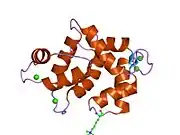

![1qiv: CALMODULIN COMPLEXED WITH N-(3,3,-DIPHENYLPROPYL)-N'-[1-R-(3,4-BIS-BUTOXYPHENYL)-ETHYL]-PROPYLENEDIAMINE (DPD), 1:2 COMPLEX](../I/PDB_1qiv_EBI.jpg.webp)